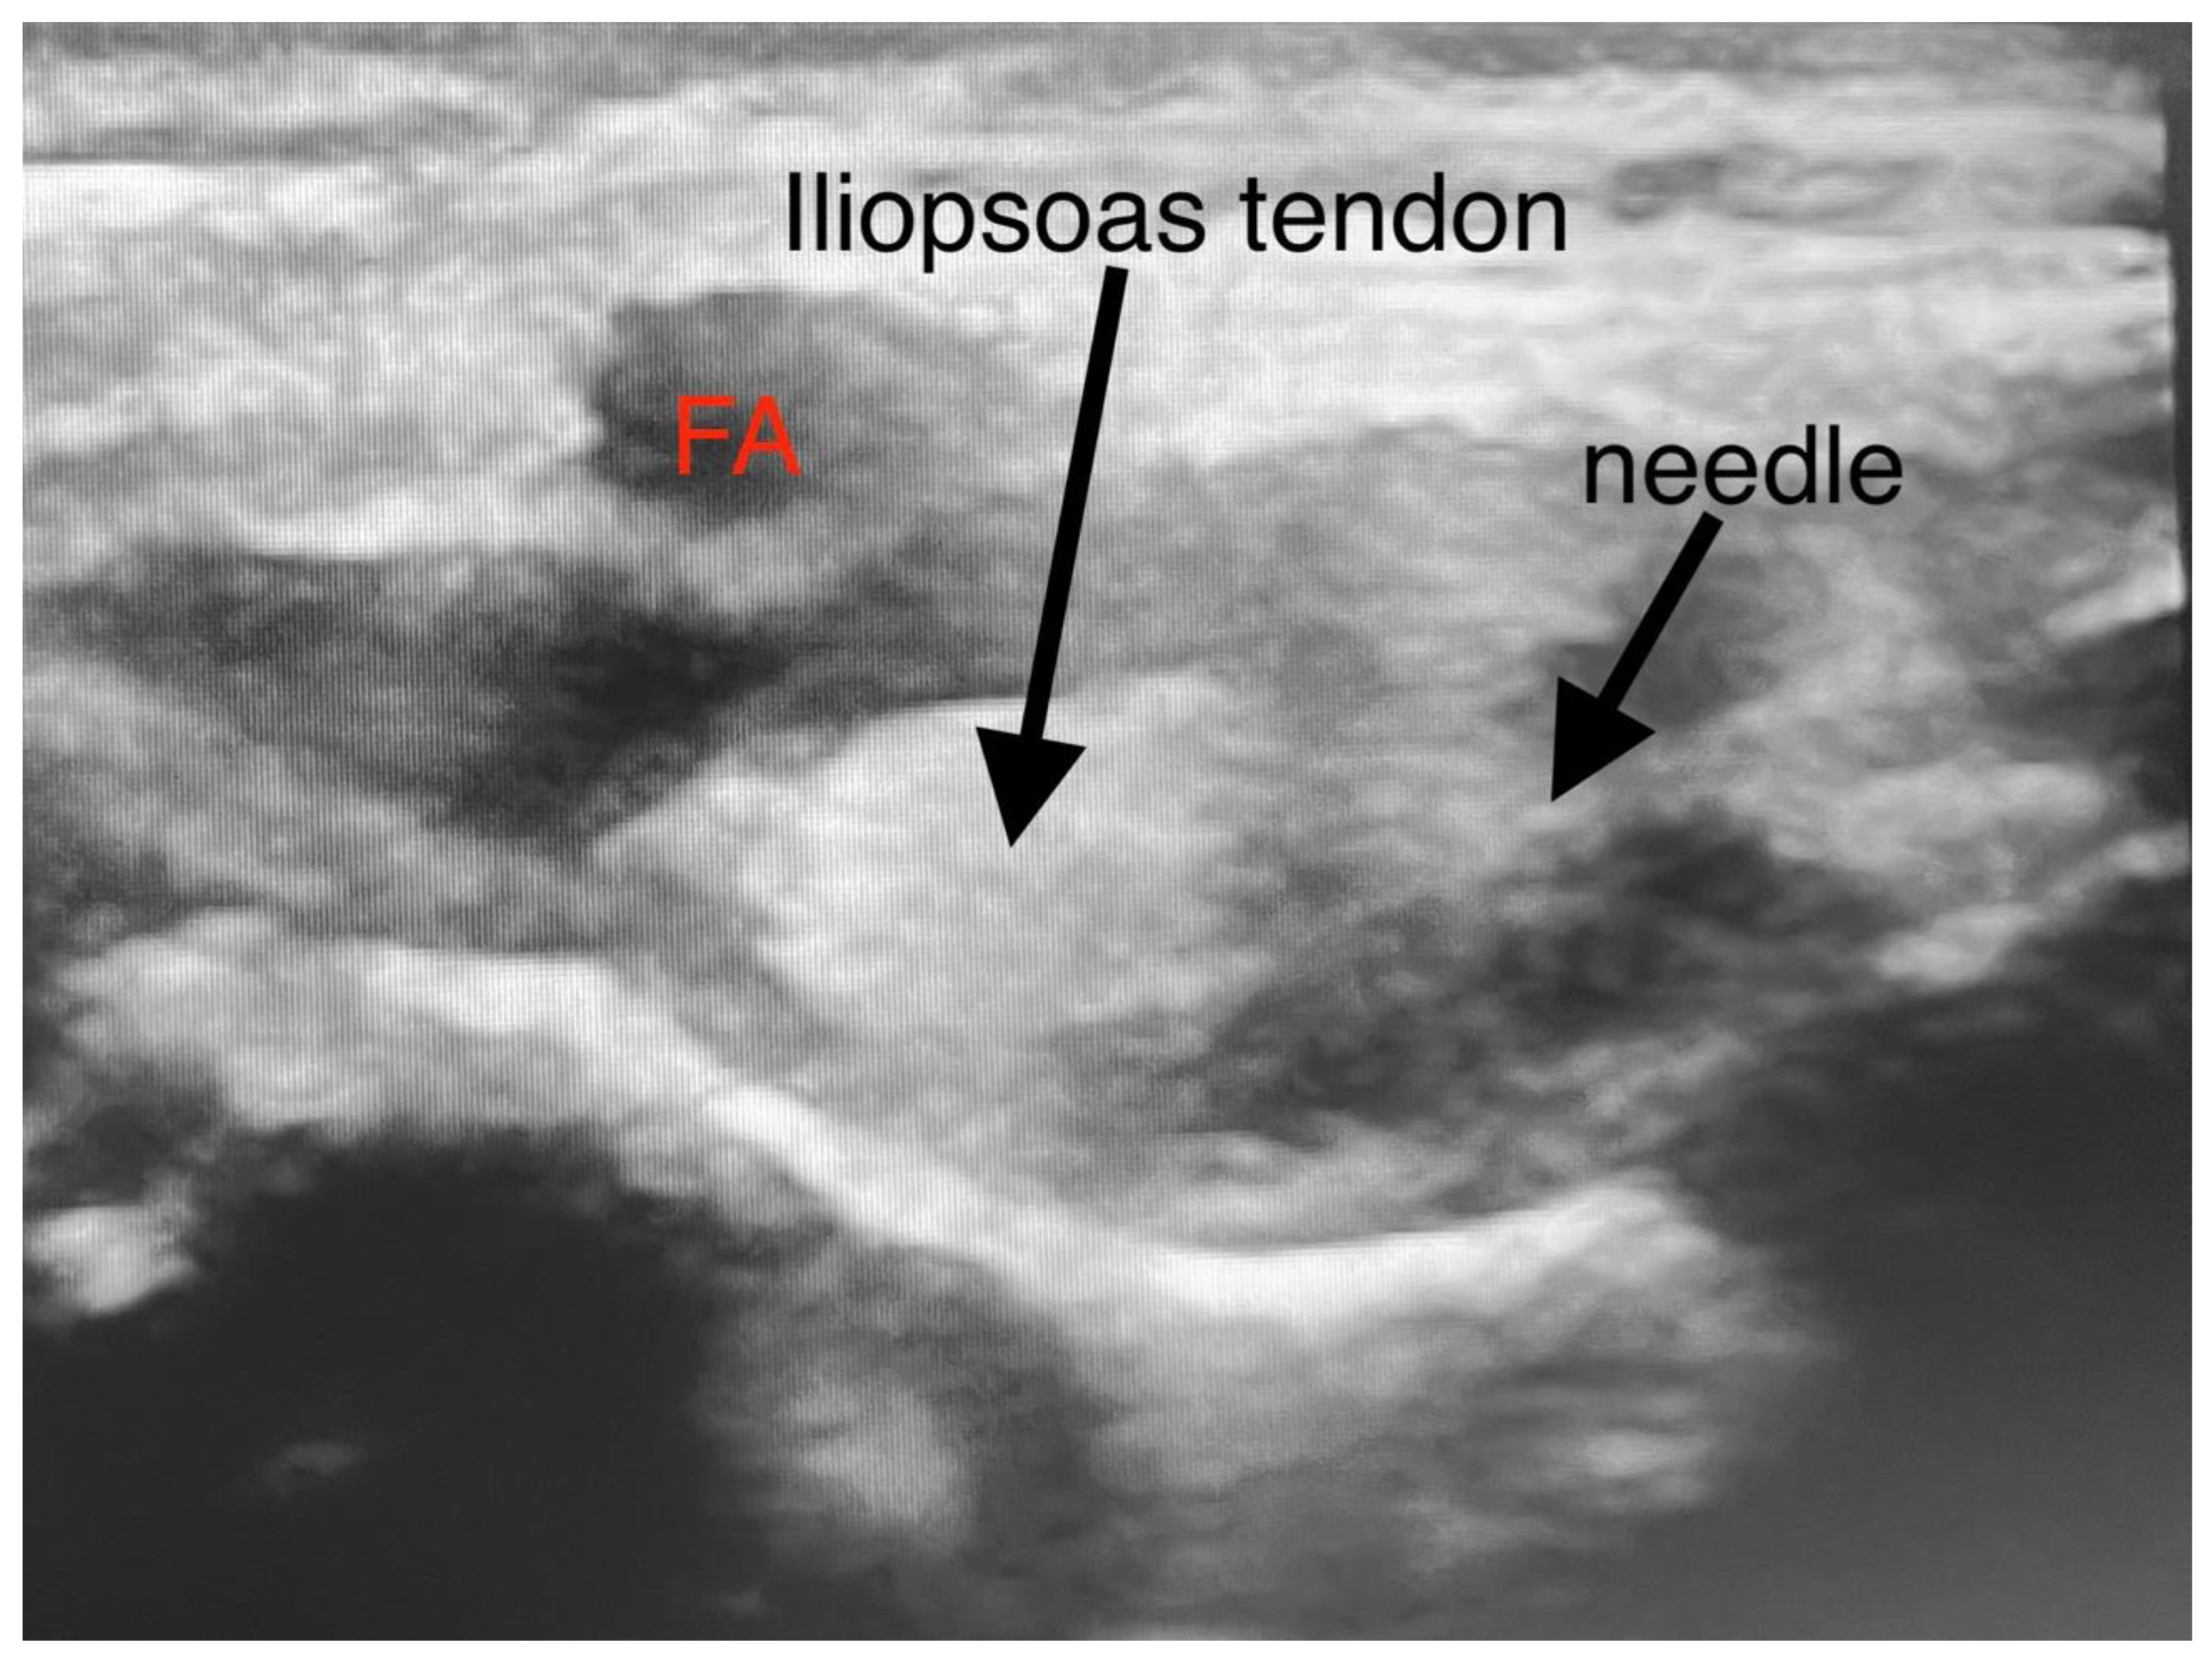

Figure 2.

Injection technique of PENG block. (FA—femoral artery).

The patients were kept supine during the focal block. A low-frequency linear transducer (2–5 MHz) was put in a transverse plane along the left anterior inferior iliac spine (AIIS) to identify the iliopsoas muscle, femoral nerve, and femoral artery (FA). The probe was then rotated counterclockwise to align with the pubic ramus to visualize the AIIS, iliopsoas prominence (IPE), FA, iliopsoas, and iliopsoas notch. Under direct vision, a 22-gauge 50 mm echo needle was advanced in the lateral-medial plane between the psoas tendon and the pubic ramus until the needle tip touched the IPE. The needle was withdrawn, and after negative aspiration, 0.2% ropivacaine was injected in incremental doses. Preparation and surgical positioning allowed for maximal time for block onset.